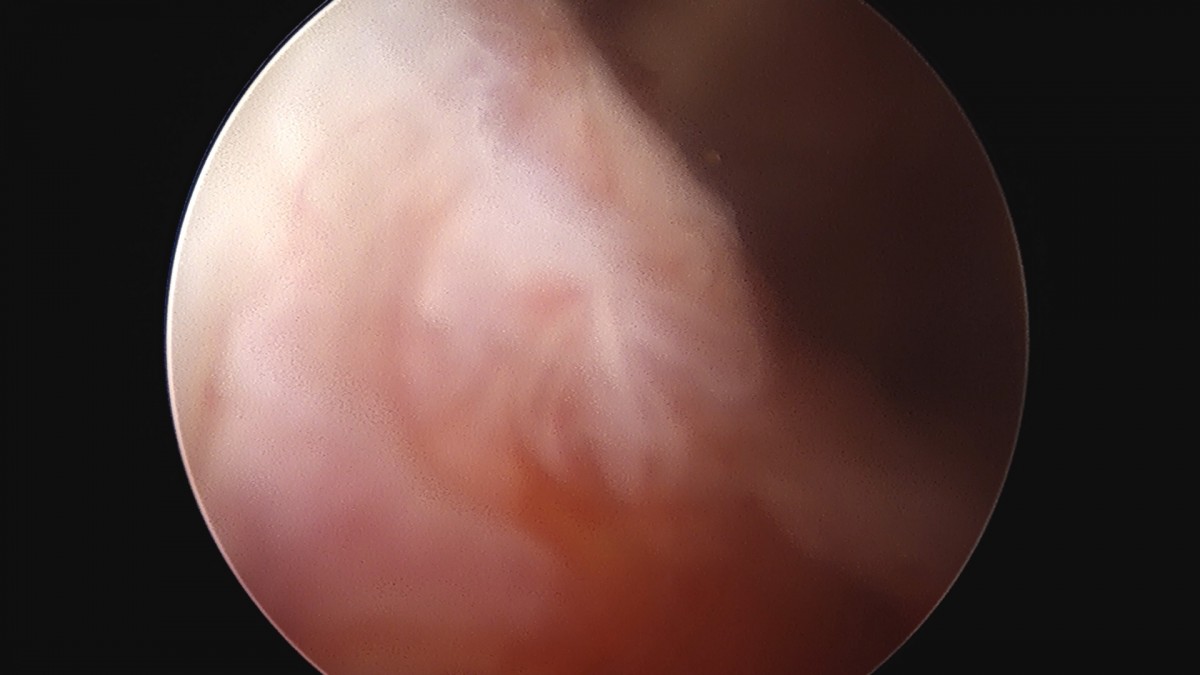

이재상원장님 어깨 견봉하 감압술 김선O 환자

dae765e4d9ac96aee867c9d6292d8784_1758004048_8969.jpg